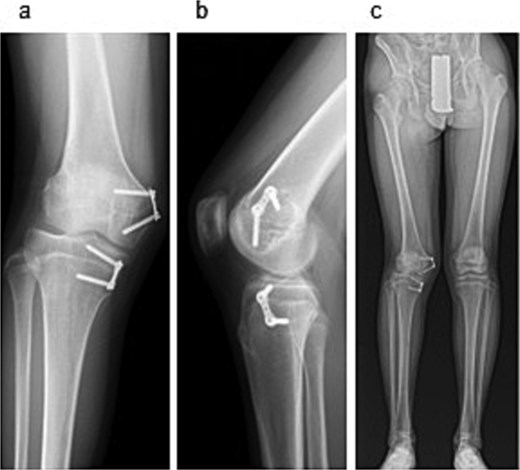

To correct the valgus deformity, an eight-plate (MC Medical Corporation, Tokyo, Japan) was inserted, across the distal medial femur and proximal medial tibia (Fig. 4c). Mild thigh swelling from the irrigation fluid occurred postoperatively; with no signs of compartment syndrome or wound complications. Weight-bearing began the next day with crutch-assisted ambulation guided by pain tolerance. He was discharged on postoperative Day 6, ambulating independently with crutches. At the 24-month follow-up, he reported no pain and improved right knee range of motion (0–140°) (Fig. 5a–c). Radiography showed that the FTA had improved to 168°.

Radiographic findings at 24-month follow-up. (a) Anteroposterior radiograph of the right knee. (b) Lateral radiograph of the right knee. (c) Full-length standing anteroposterior radiograph of the lower extremities.